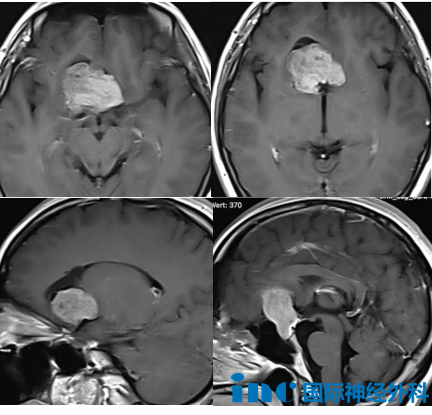

2025年平安夜,武女士接受开颅手术,手术结果令人满意:肿瘤完全切除,垂体柄成功保留,术后第一天即从ICU转至普通病房。巴特朗菲教授在术后查房时确认患者视野和视力无新发损伤,术后第三天患者可下床活动,恢复速度超出预期,伤口愈合良好。术后第四天MRI检查证实肿瘤全切,患者整体状况良好。

武女士与配偶感情稳定,在确诊脑瘤前刚完成订婚。2025年10月,患者出现幻嗅症状(突发性闻到异常气味),随后发生头痛和癫痫发作。尽管住院期间使用安定类药物治疗,仍出现多次轻微抽搐。MRI检查显示鞍区存在3.3cm×4.2cm×4.1cm巨大占位,已导致双侧大脑前动脉受压移位。

平安夜当天手术顺利实施,肿瘤完全切除的同时成功保留垂体柄。患者术后恢复迅速,第一天即确认无并发症发生,第三天可下床活动,第四天MRI确认肿瘤全切。患者表示:"术后感觉良好,与正常人无异,可能需短期激素调整,但垂体柄未受影响则问题不大。"